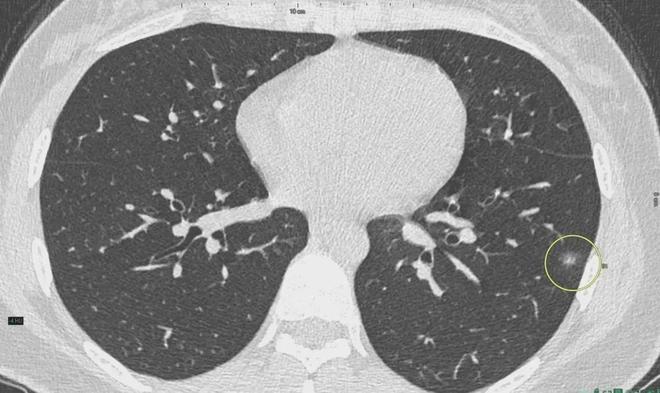

肺結(jié)節(jié)是一種常見的肺部疾病,其發(fā)病率逐年上升,雖然肺結(jié)節(jié)多數(shù)情況下是良性的,但也有可能惡化為肺癌,了解肺結(jié)節(jié)的形成原因?qū)τ陬A(yù)防和治療具有重要意義,本文將為您詳細(xì)解析肺結(jié)節(jié)的形成機(jī)制。

6、定期體檢:定期進(jìn)行肺部檢查,及時發(fā)現(xiàn)并治療肺結(jié)節(jié)。